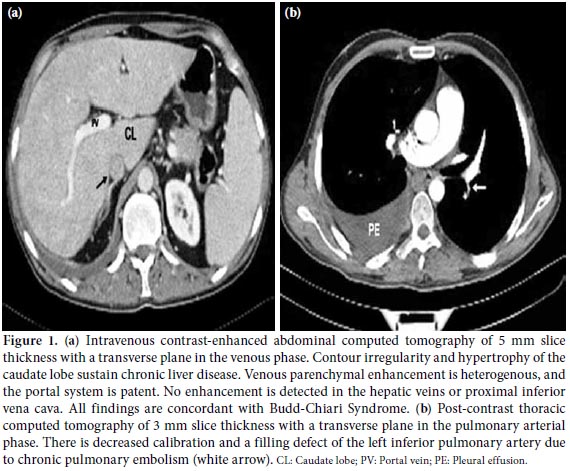

A 29-year-old male patient with BD was admitted to our clinic with dyspnea, palpitations, and chest pain. The diagnosis had been established three years earlier on the basis of mucocutaneous lesions and gastrointestinal disorders. The patient had then been treated with colchicine and corticosteroids. His past medical history also included deep venous thrombosis (DVT) in his calf. On his physical examination, a left parasternal murmur resembling the sound of a machine was detected along with abdominal ascites. His electrocardiography (ECG) and chest X-ray results were normal. Post-contrast thoracic computed tomography (CT) revealed right pulmonary effusion and decreased calibration together with a filling defect of the left inferior pulmonary artery due to a chronic PE (Figure 1a). On the abdominal ultrasononography, hepatic venous thrombosis was detected. The portal venous system was patent, but no enhancement was detected in the hepatic veins or proximal inferior vena cava (IVA) on the abdominal CT. The findings were concordant with BCS (Figure 1a). Two-dimensional transthoracic echocardiography revealed a mass on the right atrium protruding into the right ventricle (Figure 2a). The suprasternal view showed a turbulent and abnormal flow surrounding the arcus aorta and pulmonary artery (Figure 2b). Doppler interrogation demonstrated a continuous flow signal at that location. In addition, coronary angiography was performed to evaluate coronary involvement because of intractable angina pectoris, and a coronary arteryto- pulmonary artery fistula was detected arising from the left coronary artery (LCA) (Figure 3). On cardiac catheterization and oximetry study, there was a 5% step-up between the right ventricle and distal pulmonary artery, and the left-to-right shunt was 1.3. Since there was no evidence of a significant shunt, the fistula was not thought to be the cause of the angina, and the patient did not undergo corrective intervention. During the sixth month of treatment with colchicine, methylprednisolone, cyclophosphamide, and heparin, thoracic CT revealed complete lysis of the pulmonary thrombosis and ICT.